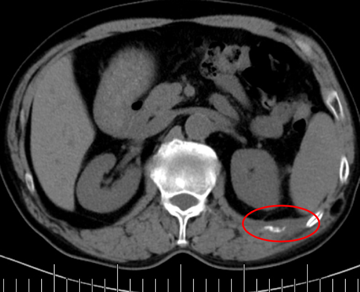

老年男性,68歲,肺癌術(shù)后肋骨轉(zhuǎn)移,痛疼難忍。

左側(cè)肋骨轉(zhuǎn)移